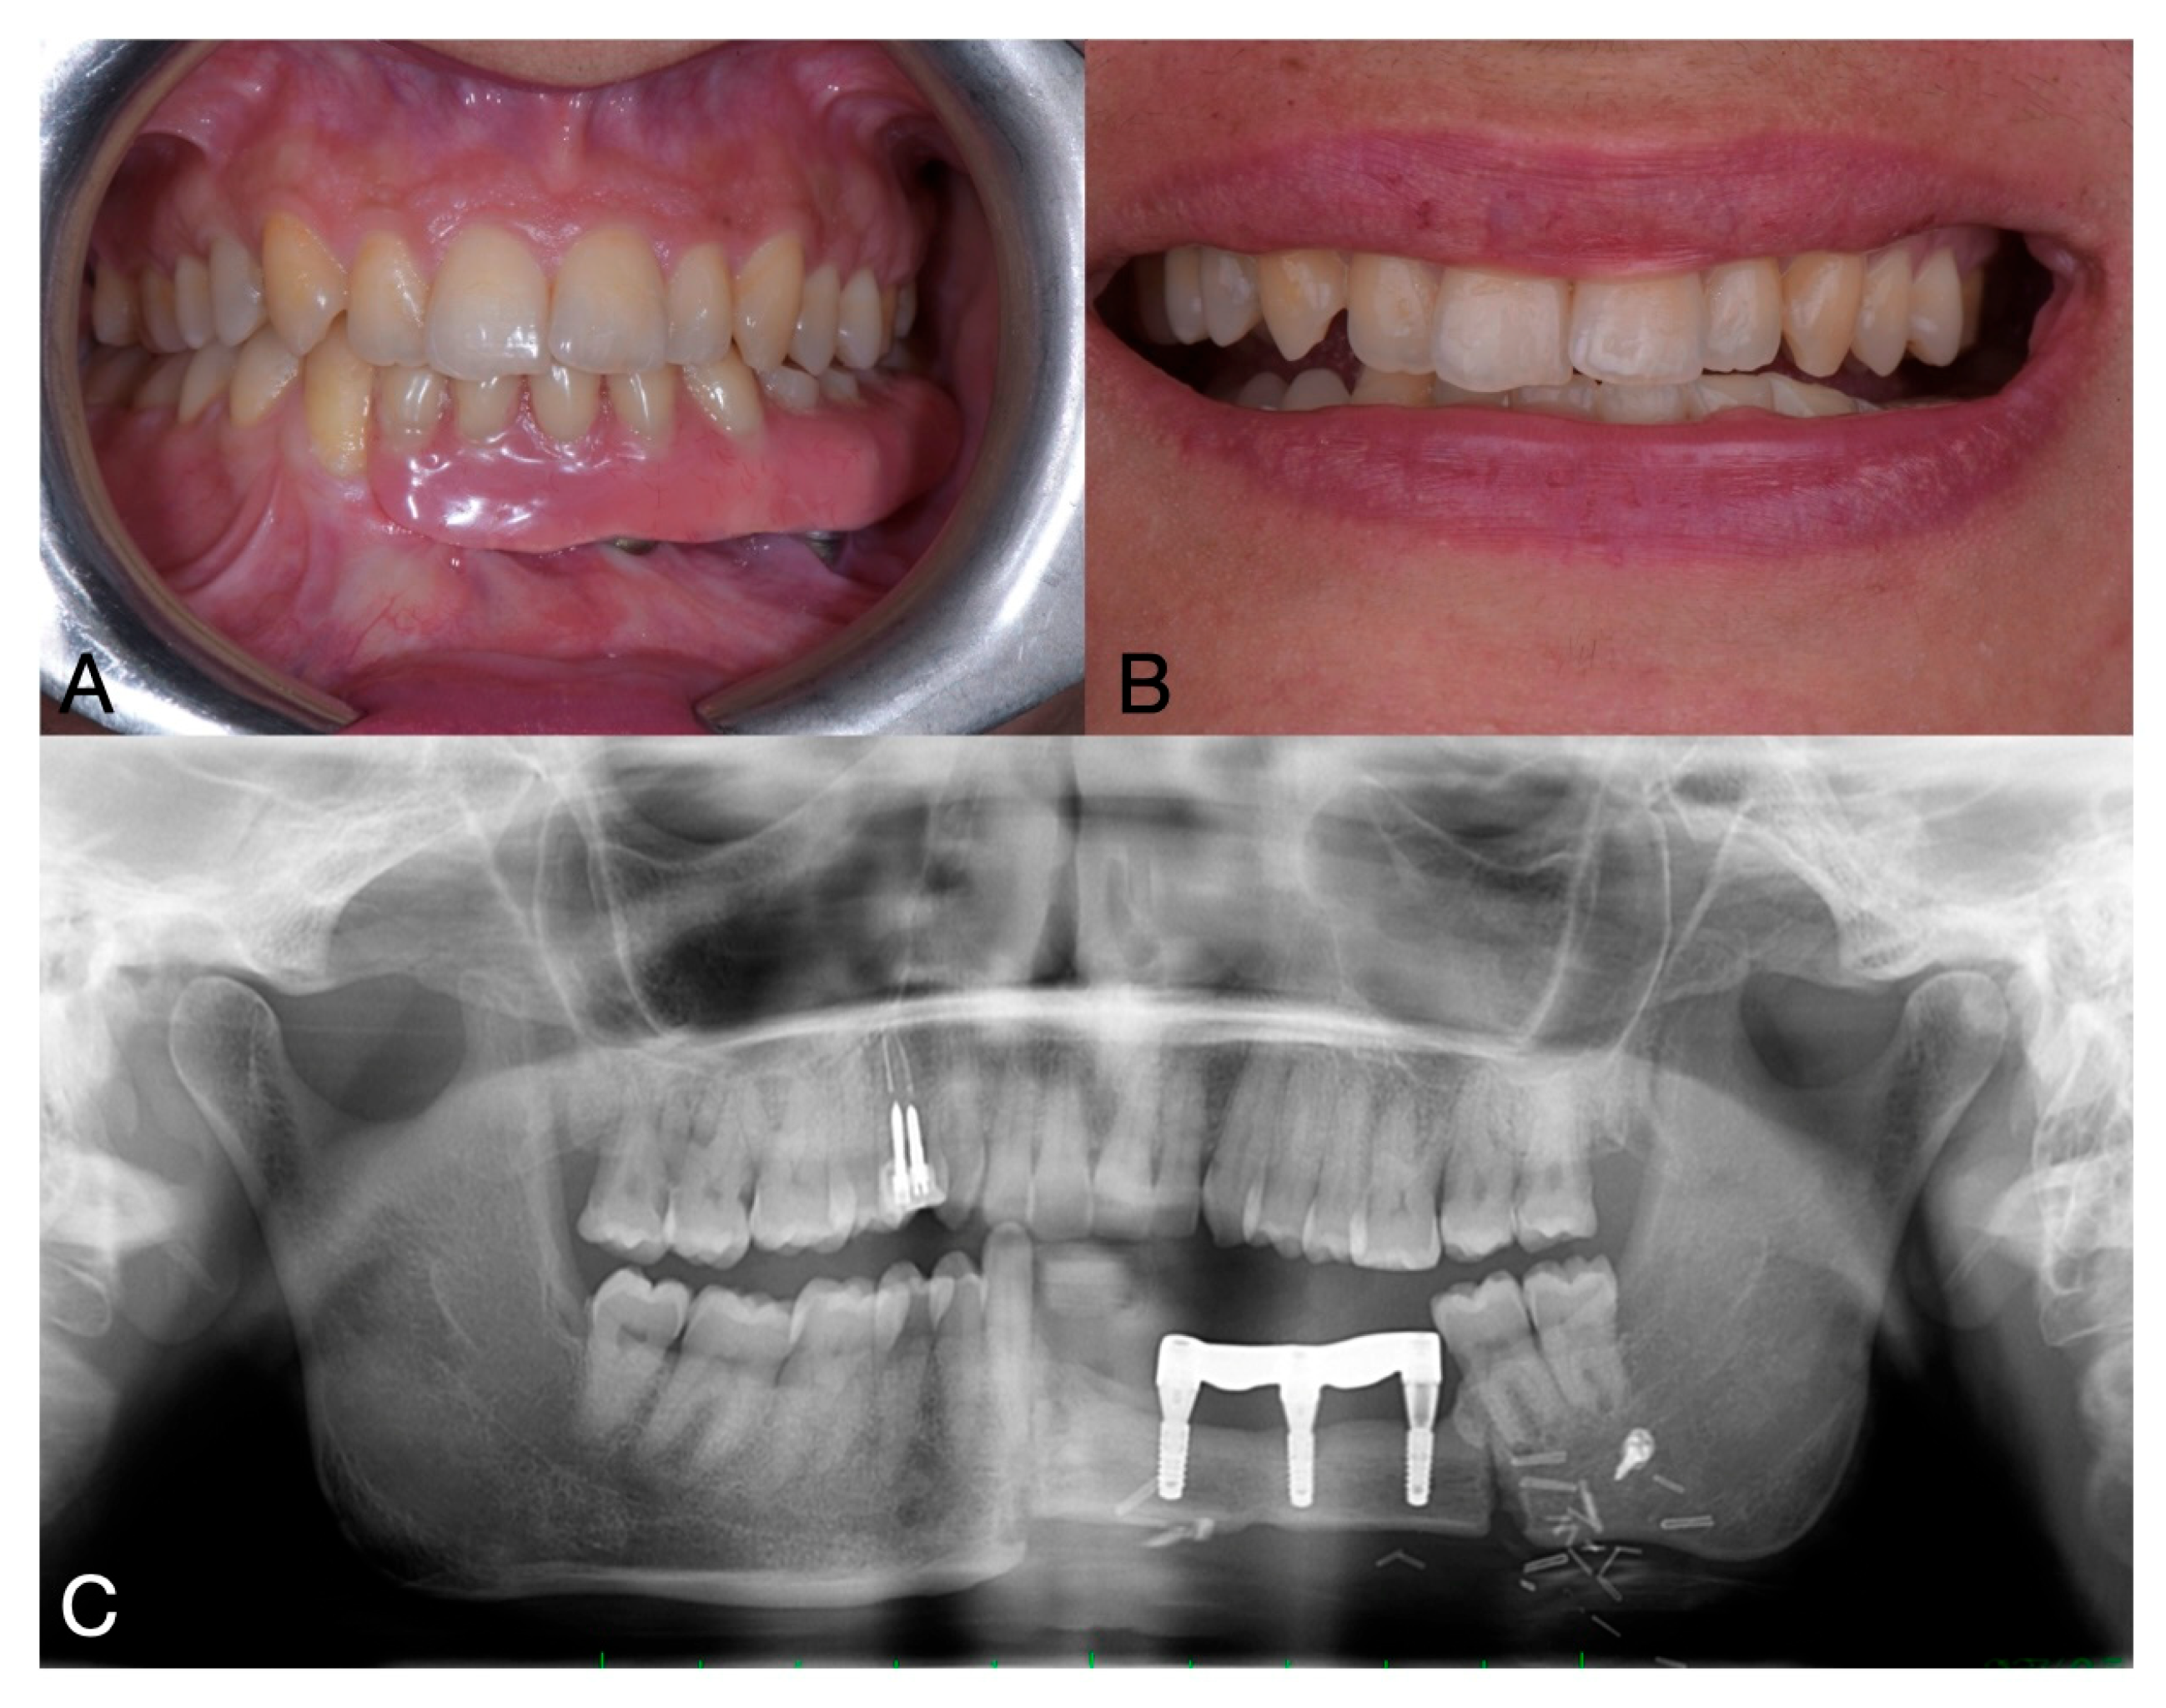

One year after the mandibular surgery, on OPG was performed to plan the subsequent implant-prosthetic rehabilitation (Figure 5).

Figure 5. Pre-operative clinical situation (A,B) and OPG (C).